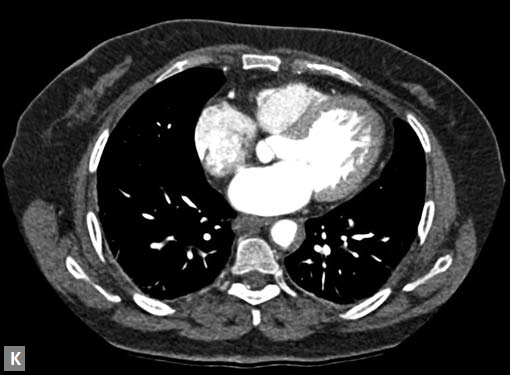

Connective tissue disease, hypertension and iatrogenic (Figs 19K to L) injury are the common causes for dissection. Radiologist not only establishes the diagnosis, also evaluates the extent of dissection, presence of thrombosis particularly in false lumen. In case of type A dissection, involvement of aortic root is determined. Relation of thrombosed lumen and ostia of coronary vessels, cephalad branches (Figs 19N, R to V) of aorta is determined. Most of the occasions membrane is demonstrated. Spiral nature of the membrane can be seen

Figs 19A to Y (A to C) Scannogram (A), plain (B) and contrast study (C) show partial anomalous pulmonary venous connection; (D to F) Heterotaxy; (G) Aortic occlusion; (H and I) Aortic stents; (J) Aortic dissection with ‘Benz’ sign due to second dissection within the true lumen; (K, L and M) Aortic dissection with thrombus in pseudolumen following catheter angiogram; (N) Aortic dissection involving common carotid arteries and subclavian artery; (O, P, Q and R) Aortic dissection with right renal artery arising from true lumen and left renal artery from false lumen; (S, T, U and V) Stanford B dissection with extension Y to iliac vessels; (W to Y) Aneurysmal dilation of ascending aorta